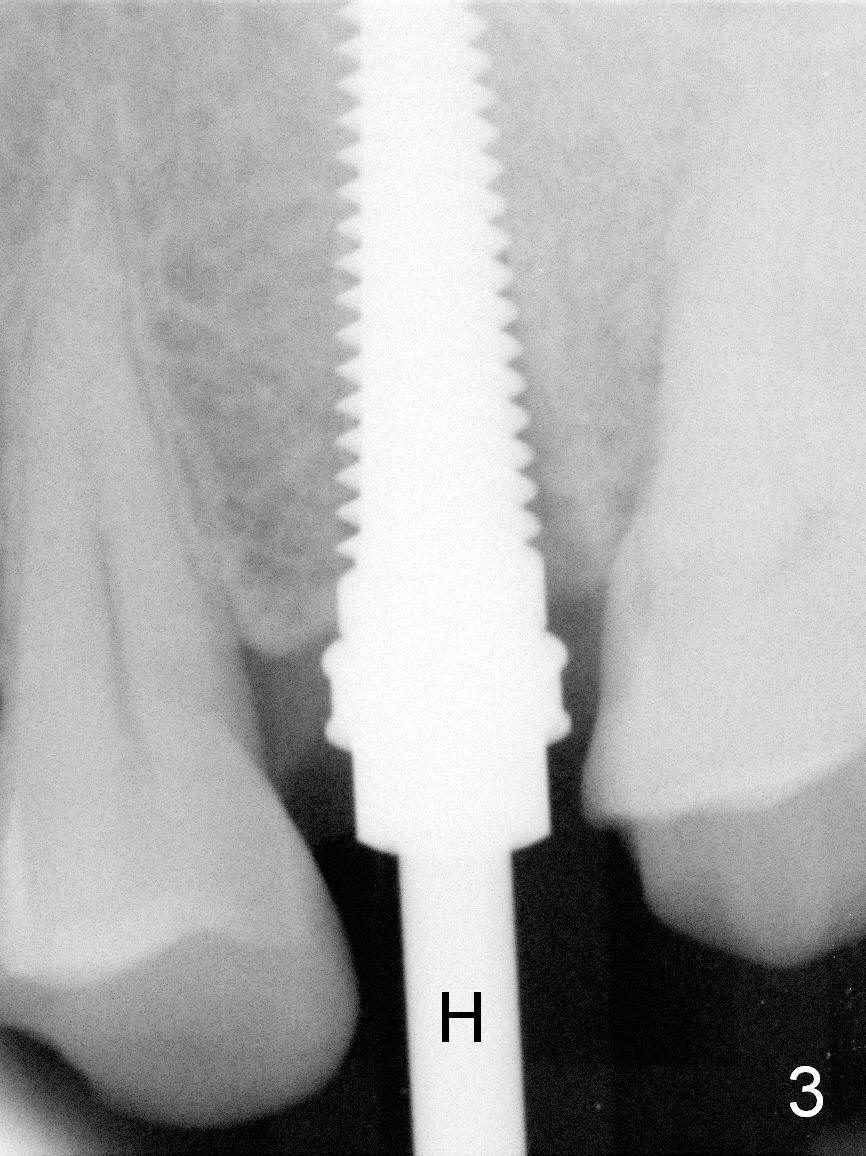

A 47-year-old man returns to clinic with chief complaint "top left tooth chips". Exam reveals subgingival fracture of the lingual cusp of the tooth #13 (Fig.1). A 4.5x17 mm tissue-level implant and 3.5x3 mm abutment appear to be appropriate for the site (Fig.2 (^: sinus floor)). After extraction and socket treatment with 1:50,000 Epinephrine gauze, a 4.5x20 mm tap is placed at the depth of 17 mm. Although the tap has achieved stability, a PA taken with it does not the superior end due to the interference of its long handle (Fig.3 H). A dummy implant (4.5x17 mm) is placed to show its approximation to the sinus floor (Fig.4). After removal of the dummy implant, the definitive implant is placed with certainty with the planned abutment (Fig.5 A). An immediate provisional is placed after bone graft and membrane.